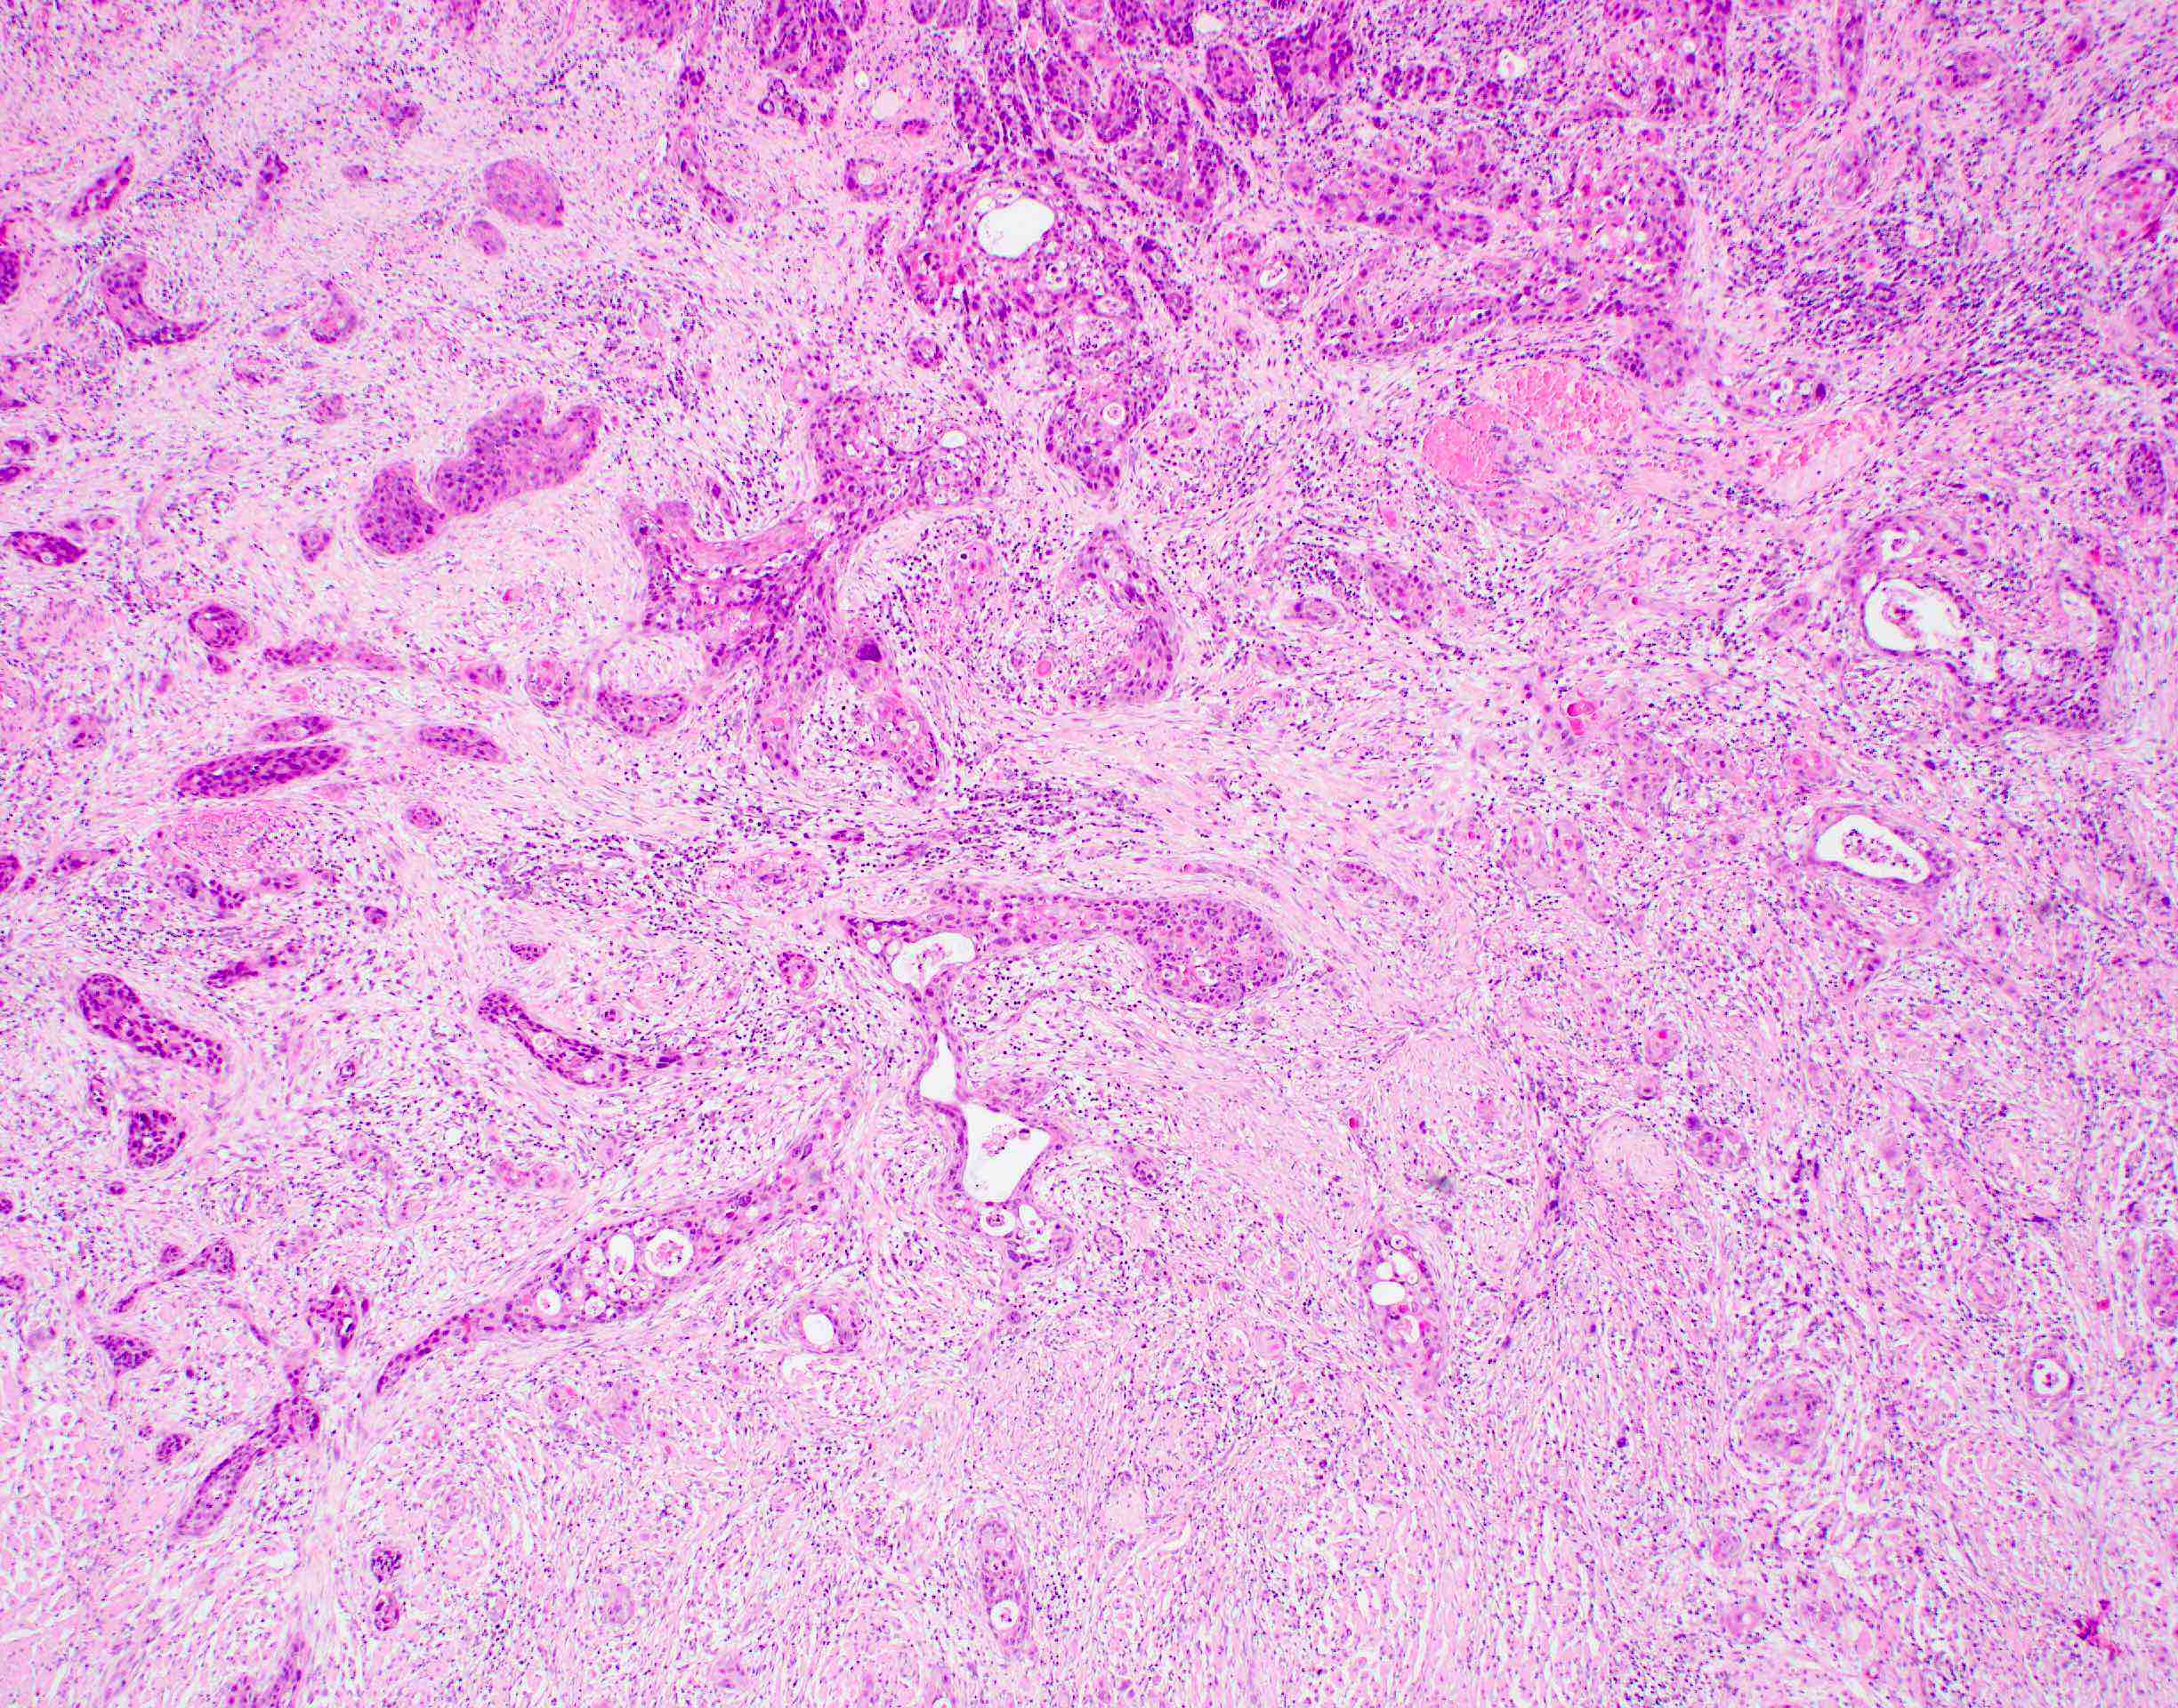

- Squamous cell carcinoma, conventional

- Most common and typical morphology of conventional keratinizing squamous cell carcinoma at any site

- Large polygonal malignant cells with intercellular bridges

- Cytoplasmic or extracellular eosinophilic keratin

- Dyskeratotic cells and squamous pearls

- Nuclear size, pleomorphism, hyperchromasia and mitoses increase with increasing grade